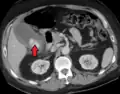

Imaging

Right upper quadrant abdominal ultrasound is most commonly used to diagnose cholecystitis.[1][26][27] Ultrasound findings suggestive of acute cholecystitis include gallstones, pericholecystic fluid (fluid surrounding the gallbladder), gallbladder wall thickening (wall thickness over 3 mm),[28] dilation of the bile duct, and sonographic Murphy's sign.[13] Given its higher sensitivity, hepatic iminodiacetic acid (HIDA) scan can be used if ultrasound is not diagnostic.[13][14] CT scan may also be used if complications such as perforation or gangrene are suspected.[14]